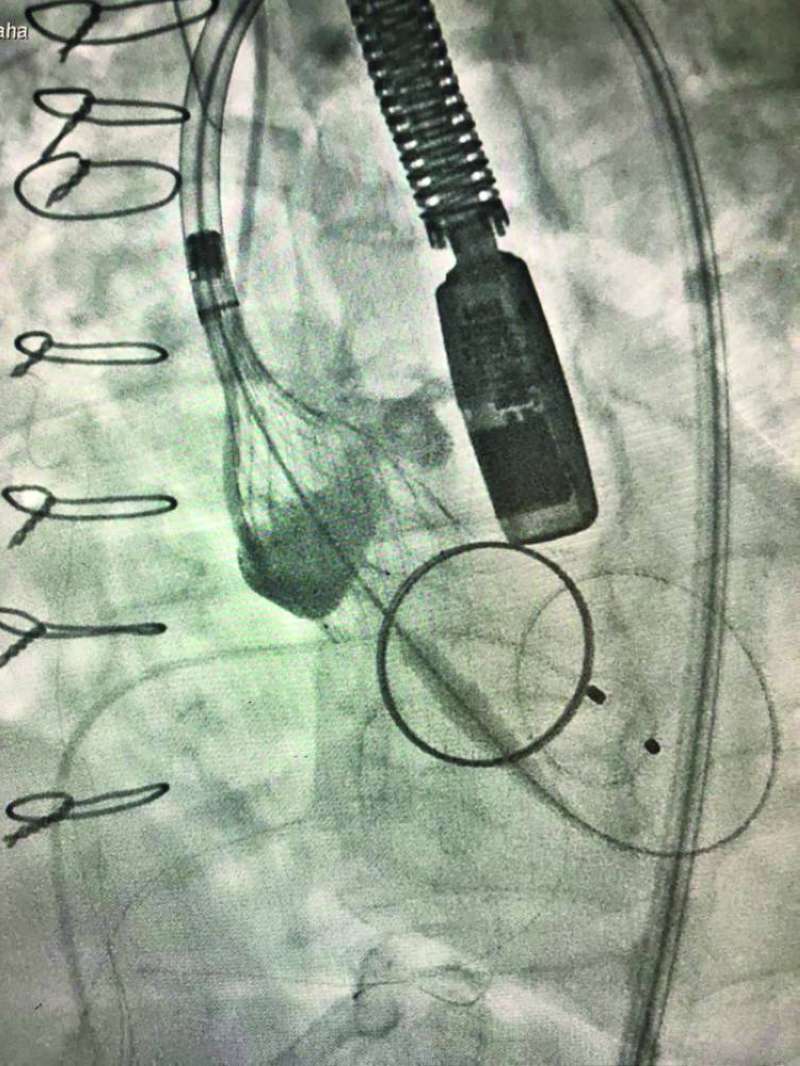

من جانبه، قال الدكتور طه لـ «الراي»، إنه «في حالة ثانية ساعدت نفس التقنية الحديثة باستخدام الصمام الجديد في تبديل صمام اورطي، ووضعه بدقة شديدة لمريض في العقد الثامن بوجود شريان أورطي مستعرض (Horizontal Aorta) بزواية إنزال تصل إلى 80 درجة، مما يسبب صعوبة شديدة في وضع الصمام بدقة في مثل هذه الحالات النادرة».